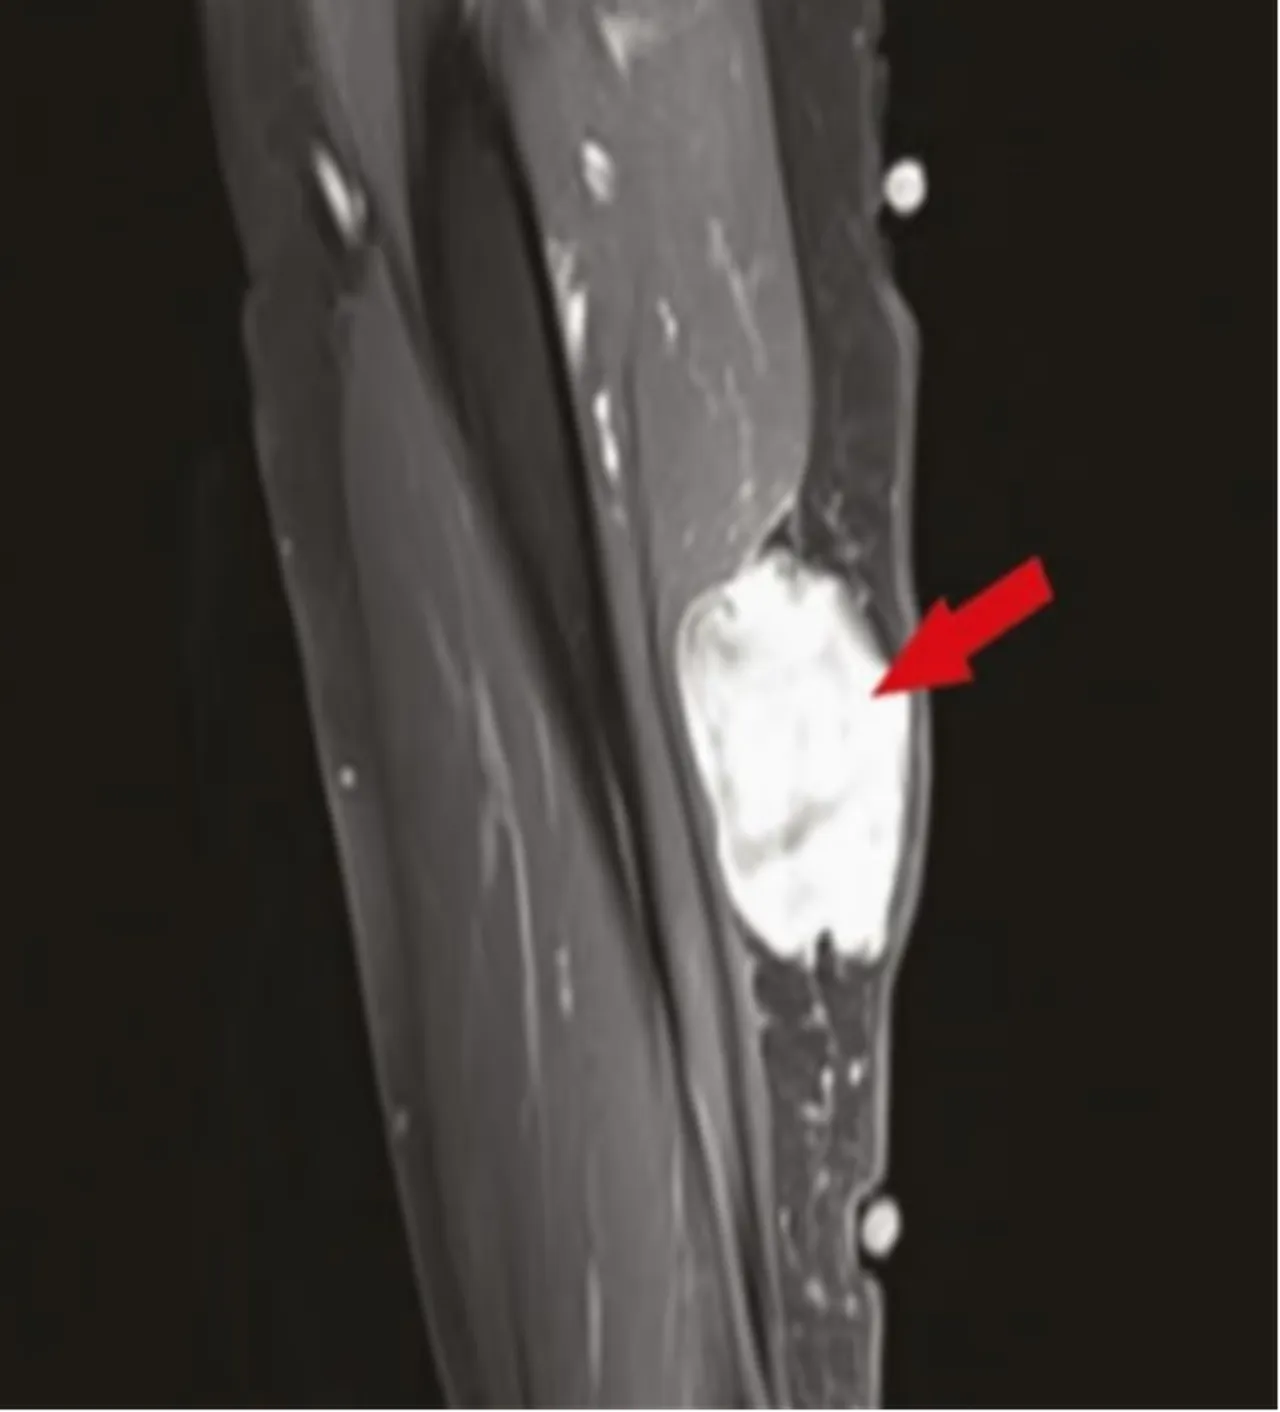

İncelemede yer alan bazı vaka raporlarında, tümörlerin aşı enjeksiyon bölgelerine yakın alanlarda ortaya çıktığı bilgisi yer aldı. Ayrıca daha önce stabil seyreden bazı kanser türlerinde ani alevlenmeler rapor edildi. Yazarlar, bu bulguların mekanizmasının anlaşılması için daha kapsamlı araştırmalara ihtiyaç olduğunu kaydetti.

Bazı uzmanlar çalışmanın Covid aşıları ile kanser arasında doğrudan bir neden-sonuç ilişkisi ortaya koymadığını yazdı. İncelemede, yalnızca daha önce yayımlanan çalışmalarda görülen ortak örüntüler bir araya getirildi. Vakaların önemli bölümünde tümörlerin enjeksiyon yapılan kol bölgesine yakın alanlarda görüldüğü aktarıldı, ancak bu durumun aşıların kansere yol açtığı anlamına gelmediği de değinilmişti.